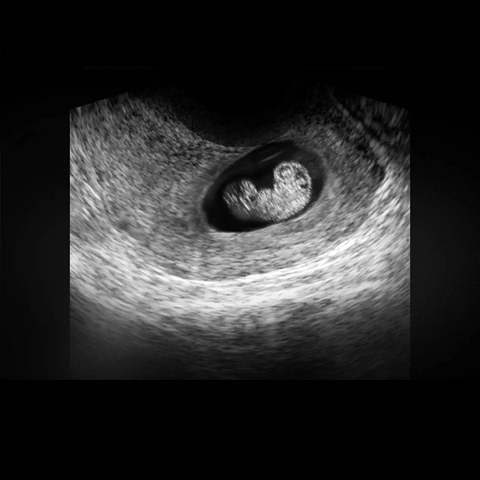

摆一个试管婴儿的故事,一定一定会刷新你的三观

过个年过得昼夜颠倒了,半夜睡不着,看到个八卦,来摆起,一个妇产科医生摆的,我偷个懒直接复制粘贴过来。今天说一个门诊试管婴儿的故事,一定一定会刷新你的三观,我从医20年,也是第一次遇到这样的。 主人公叫灵灵,之前有一次自然流产,之后全家人就特别紧张,怕怀不了了,这次就去做了试管婴儿。